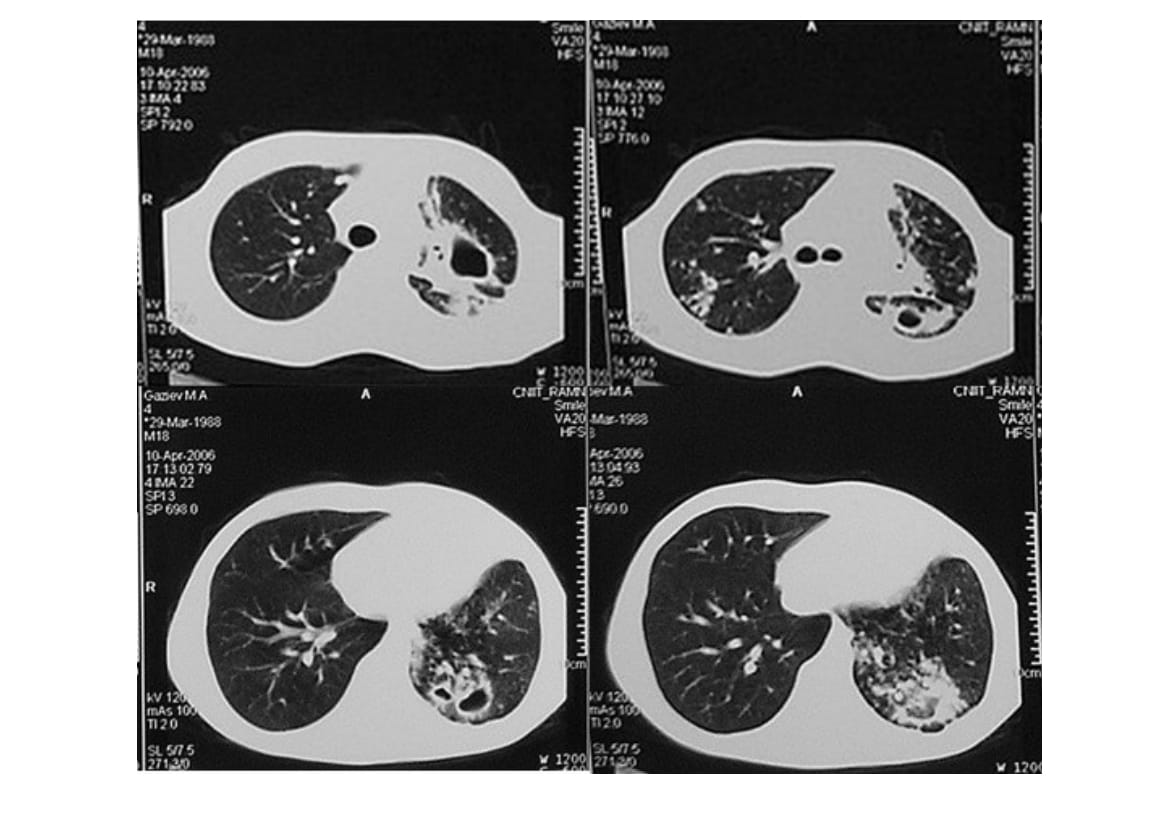

Patient G., 32 years of age, suffering from fibro-cavernous tuberculosis of the right lung in the phase of progression (Fig. 1) has been treated for 6 months conservatively with no effect, multiple drug resistance of Mycobacterium tuberculosis was detected. Pneumonectomy was performed, which revealed enlarged indurated and adherent to the surrounding tissues paratracheal, subcarinal and periesophageal lymph nodes (Fig. 2). Mediastinal lymphadenectomy was performed. On the cross-section of lymph node massive caseation was found (Fig. 3). Morphological analysis showed the presence of dry amorphous detritus with lymphoid elements and of single epithelioid cells in the peripheral areas (Fig. 4).

Fig. 1. Computed tomography of patient G. Multiple caverns in the right lung with marked perifocal infiltration